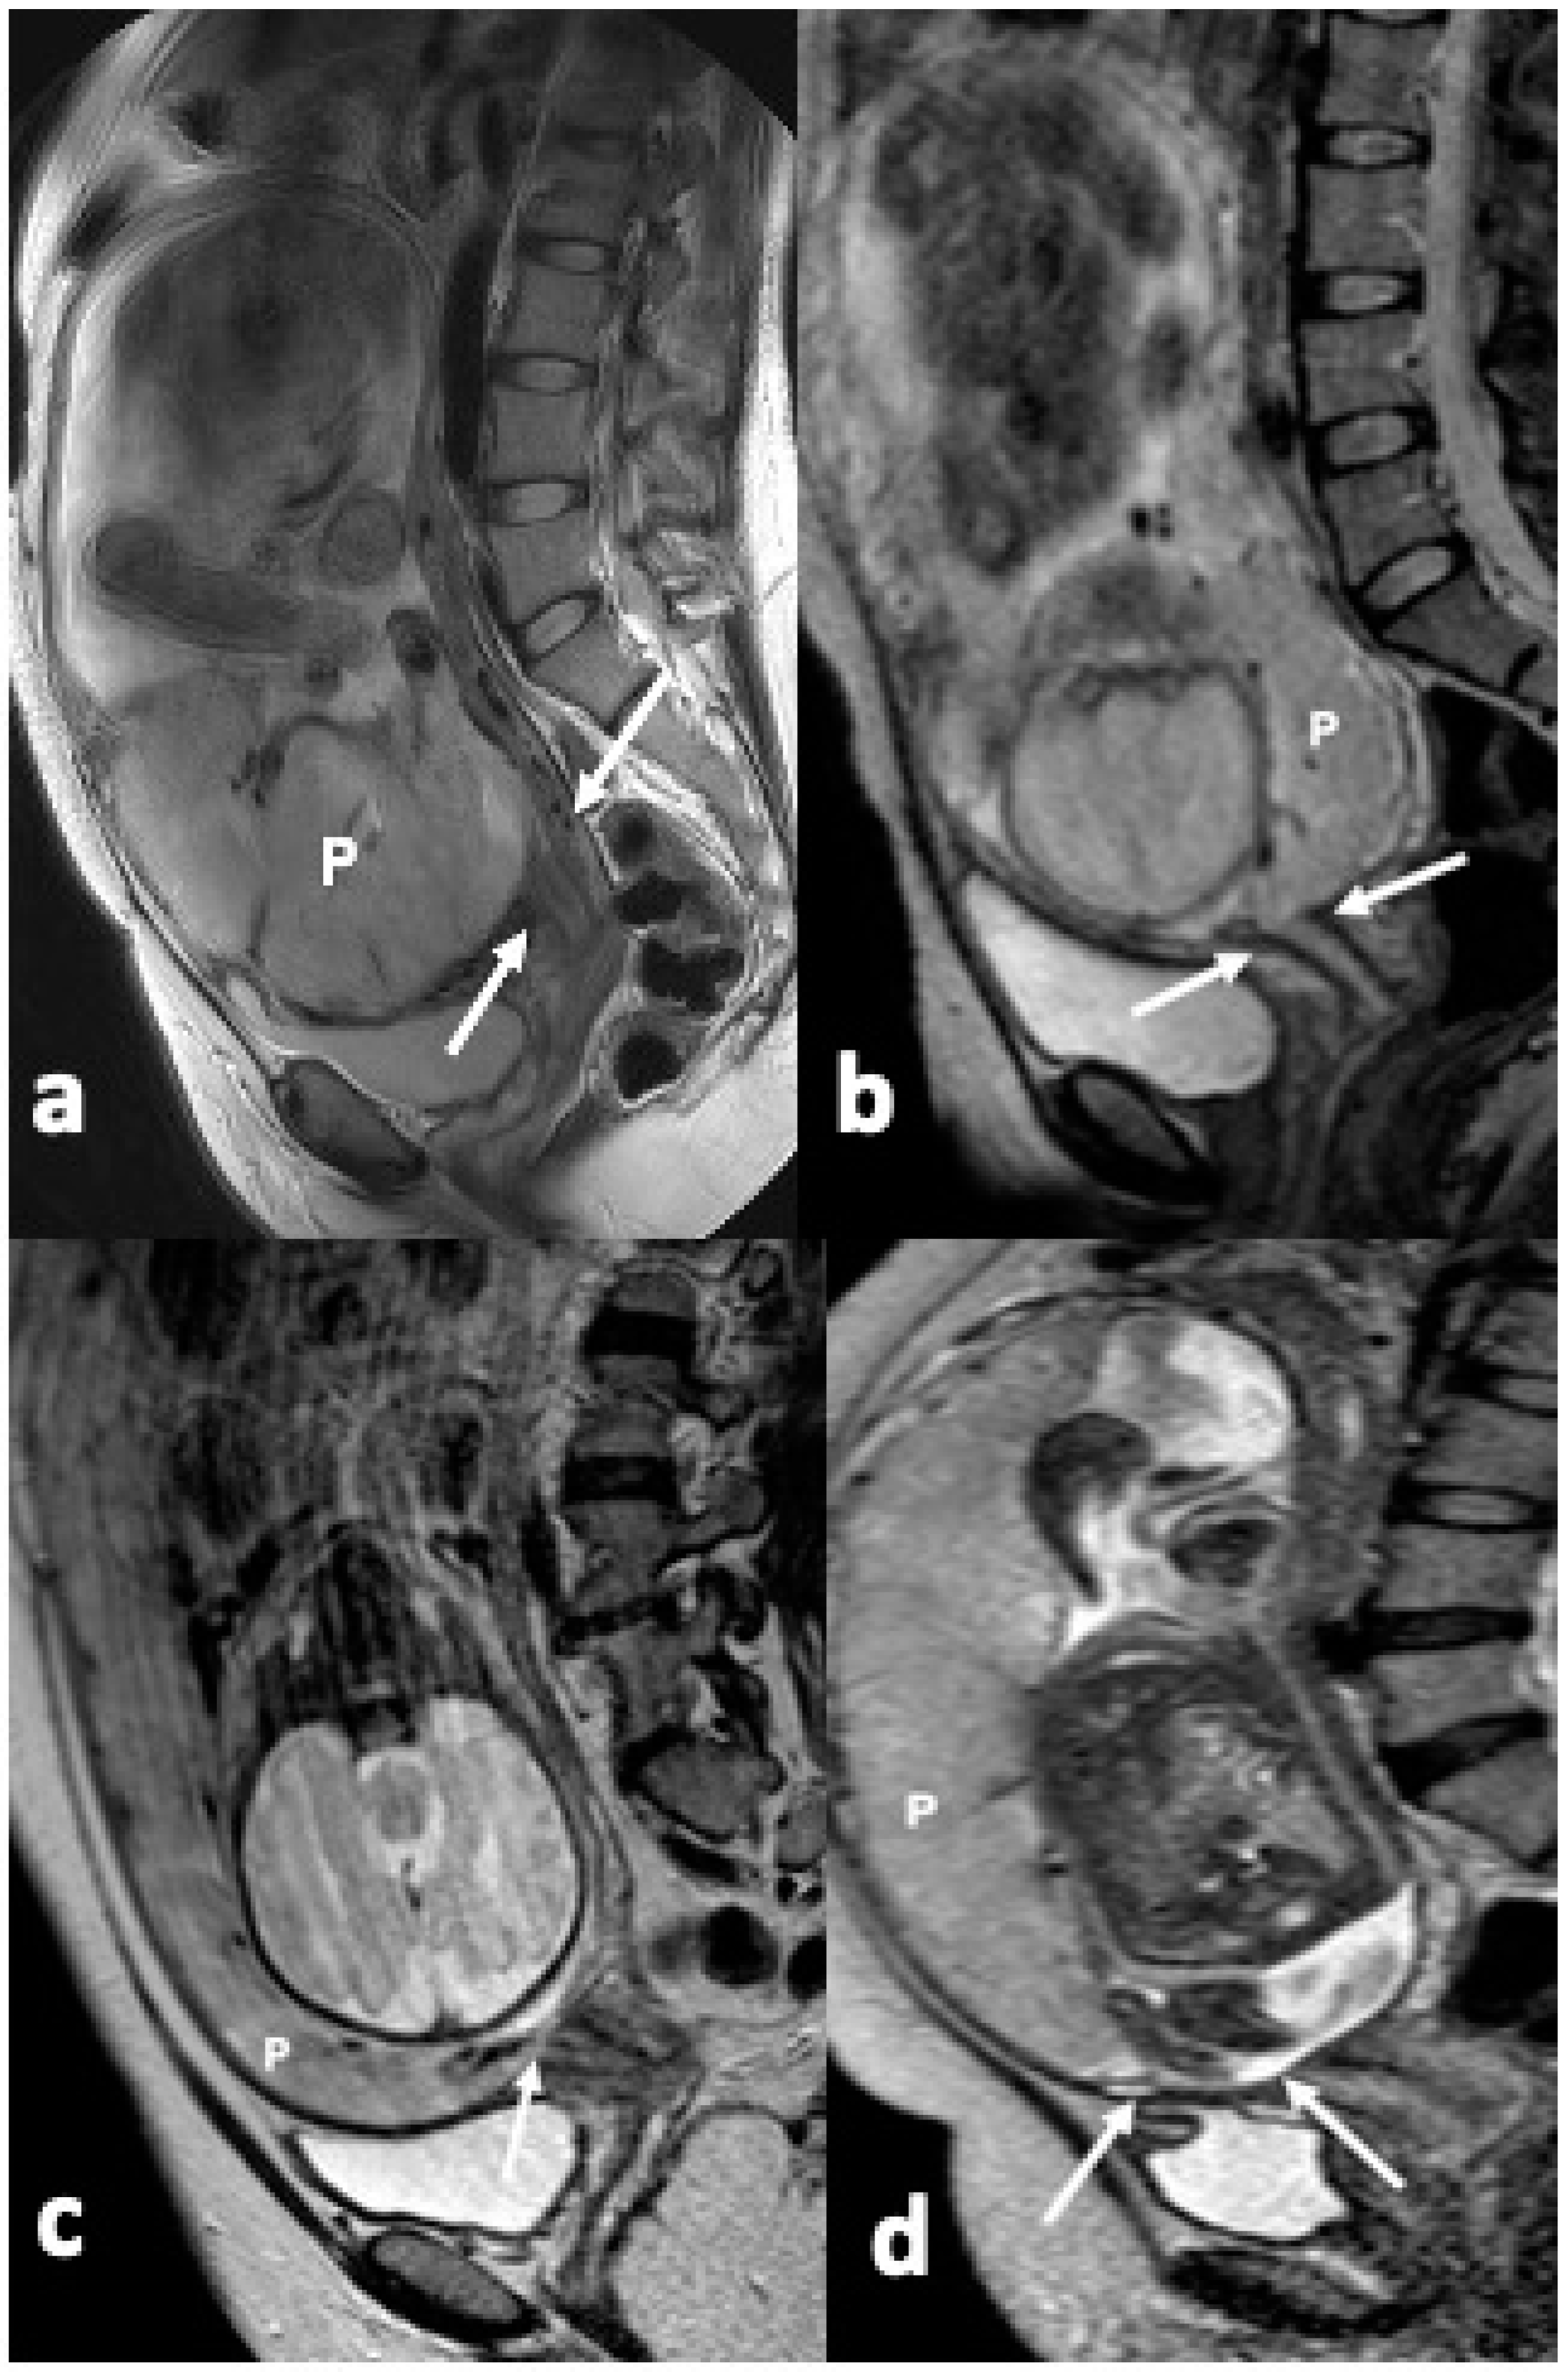

- Bourgioti, C.; Zafeiropoulou, K.; Fotopoulos, S.; Nikolaidou, M.E.; Antoniou, A.; Tzavara, C.; Moulopoulos, L.A. MRI Features Predictive of Invasive Placenta with Extrauterine Spread in High-Risk Gravid Patients: A Prospective Evaluation. Am. J. Roentgenol. 2018, 211, 701–711. [Google Scholar] [CrossRef]

- Bourgioti, C.; Zafeiropoulou, K.; Fotopoulos, S.; Nikolaidou, M.E.; Theodora, M.; Daskalakis, G.; Tzavara, C.; Chatoupis, K.; Panourgias, E.; Antoniou, A.; et al. MRI Prognosticators for Adverse Maternal and Neonatal Clinical Outcome in Patients at High Risk for Placenta Accreta Spectrum (PAS) Disorders. J. Magn. Reson. Imaging 2019, 50, 602–618. [Google Scholar] [CrossRef]

- Bourgioti, C.; Konstantinidou, A.E.; Zafeiropoulou, K.; Antoniou, A.; Fotopoulos, S.; Theodora, M.; Daskalakis, G.; Nikolaidou, M.E.; Tzavara, C.; Letsika, A.; et al. Intraplacental Fetal Vessel Diameter May Help Predict for Placental Invasiveness in Pregnant Women at High Risk for Placenta Accreta Spectrum Disorders. Radiology 2021, 298, 403–412. [Google Scholar] [CrossRef]